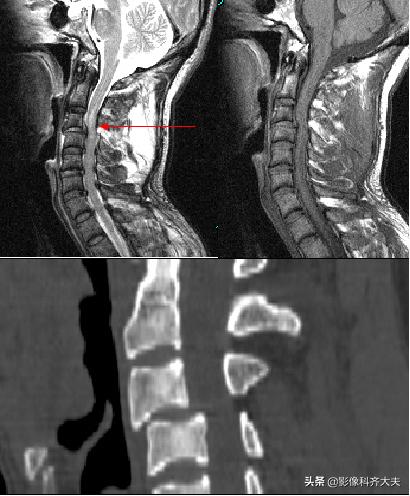

CT检查:

可见骨折椎体内出现横行、纵行、斜行、丫形等形态的骨折线

严重椎体骨折可出现“崩裂”状,表现为多数长短不等骨折线,酷似用力打碎的石板,使椎体分裂成大小不等骨块

椎体后缘骨折,可见游离在椎管内的骨折块大小、形态及位置

当附件骨折X线片显示不清时,CT检查可明确诊断

枢椎骨折

枢椎骨折矢状面重建

MRI检查

MRI矢状面枢椎骨折压迫脊髓

颈椎滑脱骨折脊髓挫伤